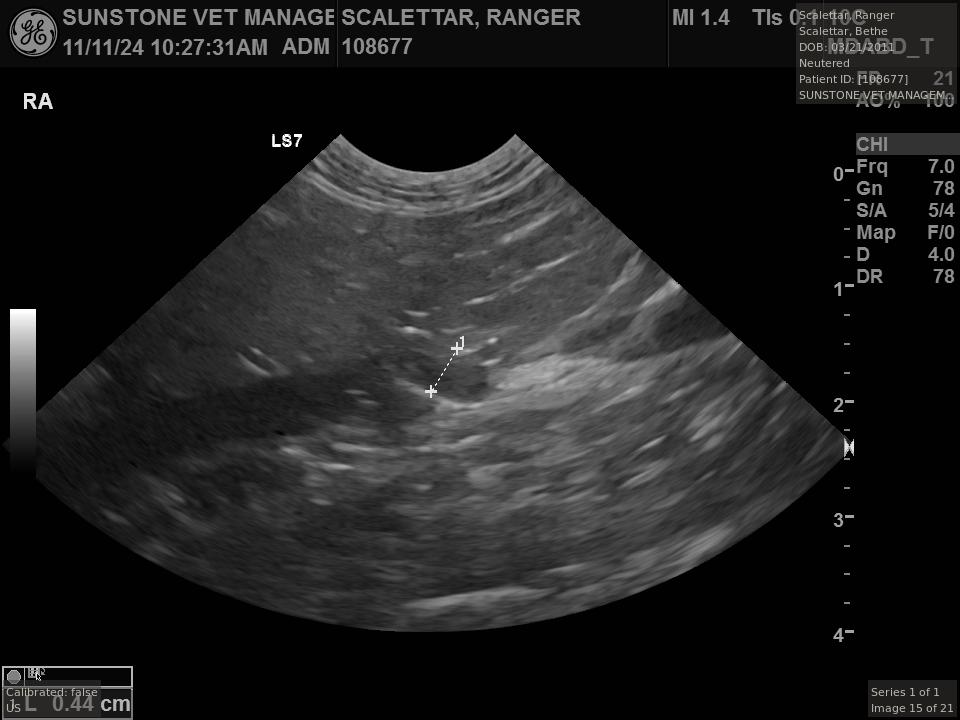

The veterinarian generated a series of images showing different organs and substructures by

changing the position and orientation of the ultrasound transducer. The images were collected

in a defined order, which is repeated from patient to patient, ensuring that nothing is missed. In

Ranger's case, the sonographer collected about twenty images during an examination that

lasted about fifteen minutes.

The sonographer stated that Ranger's ultrasound images were largely normal for an older cat. In particular, they show changes in the kidneys that are commonly noted in geriatric cats and that reflect a risk for the development of chronic kidney disease. However, the images did not show any significant abnormalities in Ranger's stomach, intestines, and associated lymph nodes. Nonetheless, the results did not rule out recurrence of Ranger's small cell lymphoma.